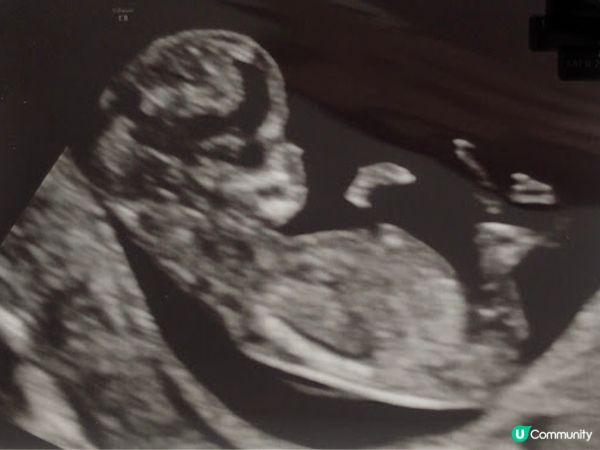

[英國懷孕記21/22] 我的孕初期 迎來了小生命 Week 1 - Week 12